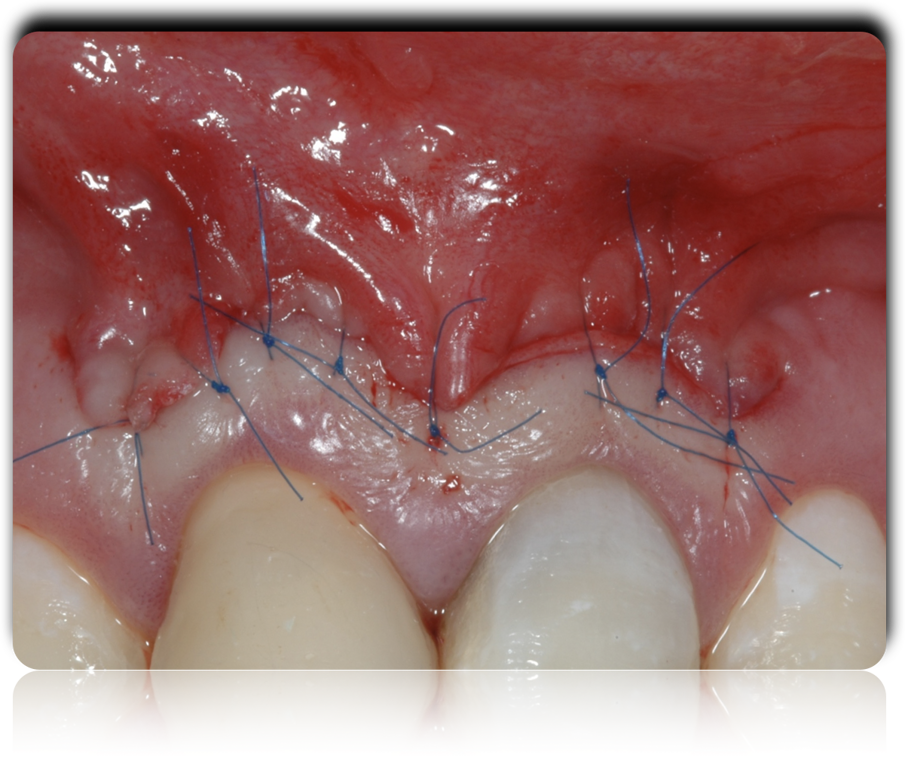

La paziente però alla presentazione del progetto, ha sollevato dei problemi in merito al trattamento ortodontico, per cui per poter esporre il tessuto sano dell’11 ed ottenere un’estetica soddisfacente, ci ha costretto ad eseguire un intervento di chirurgia più esteso da 13 a 23, pre finalizzazione protesica.

Fig. 7 - La sutura al termine dell’intervento.